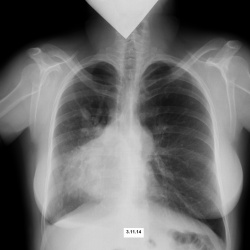

Пациент молодой, жалоб нет, очень хочет работать, но никак рука не поднимится написать норму. Попросила его зайти за результатом в понедельник. Прошу вашего мнения. Заранее благодарю.

Мужчина 1974 г.р. Жалоб нет Архива нет. Со слов, флюорографию проходит регулярно (Сельский житель. На выездном флюорографе из ОТД.) Раньше на дообследование не приглашали.